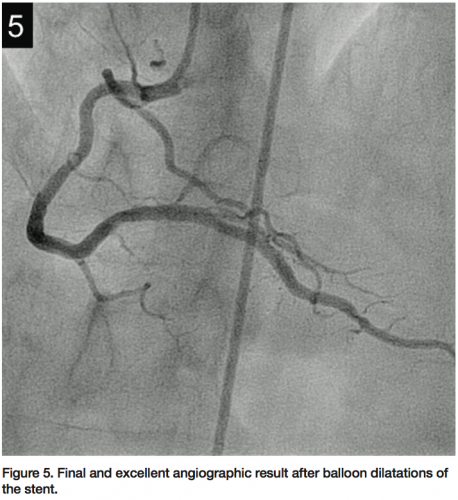

Imaging) was then performed, showing a “cheese-like” or “spider web-like” structure composed of highly reflective material throughout the stent (Figures 2A–2C). This “spider web-like” occlusive thrombus did not induce shadowing of distal structures and stent expansion could be readily identified. Moderate underexpansion (expansion of 76%) of its distal segment was recognized (measured as the ratio of minimal stent cross-sectional area divided by the mean of proximal and distal reference lumen areas). However, strut malapposition was not detected. Then, an aspiration catheter (ExportAP, Medtronic) was successfully used with improvement of coronary blood flow after retrieval of a large amount of a distinct “white” thrombotic material (Figures 3A and 3B). Finally, the stent was postdilated with a 3.5 x 14 mm Mercury balloon (Abbott Vascular, Abbott Park, Illinois) at 18 atmospheres. Postdilation, OCT showed improved expansion of the stent (stent expansion of 95%) and marked reduction of the thrombotic load, although some persistent thrombus lining apposed to the stent struts was evident (Figures 4A and 4B). An excellent angiographic result with a TIMI III coronary flow was eventually obtained, with mild transient flow deterioration of the posterolateral branch (Figure 5). Clinical course was uneventful and no rise in cardiac markers was detected.